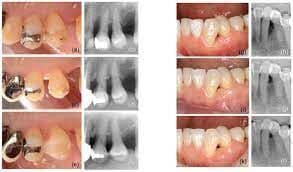

59 bemorda 74 ta intraosseous nuqsonlar regenerativ davolanishdan keyin 6 oy va 4 yil ichida baholandi. 6 oylik CAL o'zgarishi va tekshirish chuqurligi (PD) asosida nuqsonlar quyidagicha tasniflandi: COM1 (CAL daromadi ≥3 mm, PD ≤4 mm); COM2 (CAL daromadi <3 mm, PD ≤4 mm); COM3 (CAL daromadi ≥3 mm, PD>4 mm); yoki COM4 (CAL daromadi <3 mm, PD >4 mm). COM guruhlari 4 yil ichida "barqarorlik" (ya'ni, KAL ortishi, KALda o'zgarish yo'qligi yoki KAL yo'qolishi <1 mm) uchun taqqoslandi. Shuningdek, guruhlar PD va CAL ning o'rtacha o'zgarishi, jarrohlik davolashga bo'lgan ehtiyoj va tishlarning omon qolishi uchun taqqoslandi.

4 yil davomida COM1, COM2, COM3 va COM4 guruhlaridagi barqaror nuqsonlarning nisbati mos ravishda 69,2%, 75%, 50% va 28,6% ni tashkil etdi, bunda COM1, COM2 uchun barqarorlikni ko‘rsatish uchun nuqson ehtimoli ancha yuqori edi. , va COM3 COM4 bilan solishtirganda (mos ravishda 4,6, 9,1 va 2,4 nisbat). COM4 da jarrohlik qayta aralashuvlarning yuqori tarqalishi va tishlarning omon qolish darajasining pastligi kuzatilgan bo'lsa-da, COM guruhlari orasida sezilarli farqlar aniqlanmadi.